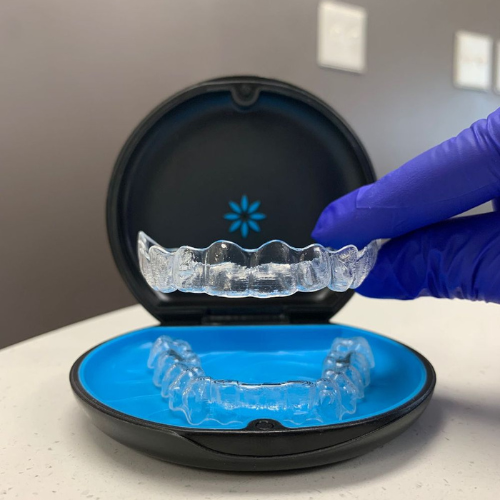

ALINHADORES INVISALIGN®

A tecnologia Invisalign® permite um planejamento ortodôntico digital personalizado a partir de escaneamento intraoral. Usando o ClinCheck, é possível prever o movimento de cada dente através de uma sequência de alinhadores feitos sob medida. Discretos, confortáveis e removíveis, os alinhadores Invisalign® oferecem resultados previsíveis sem impactar o seu estilo de vida.